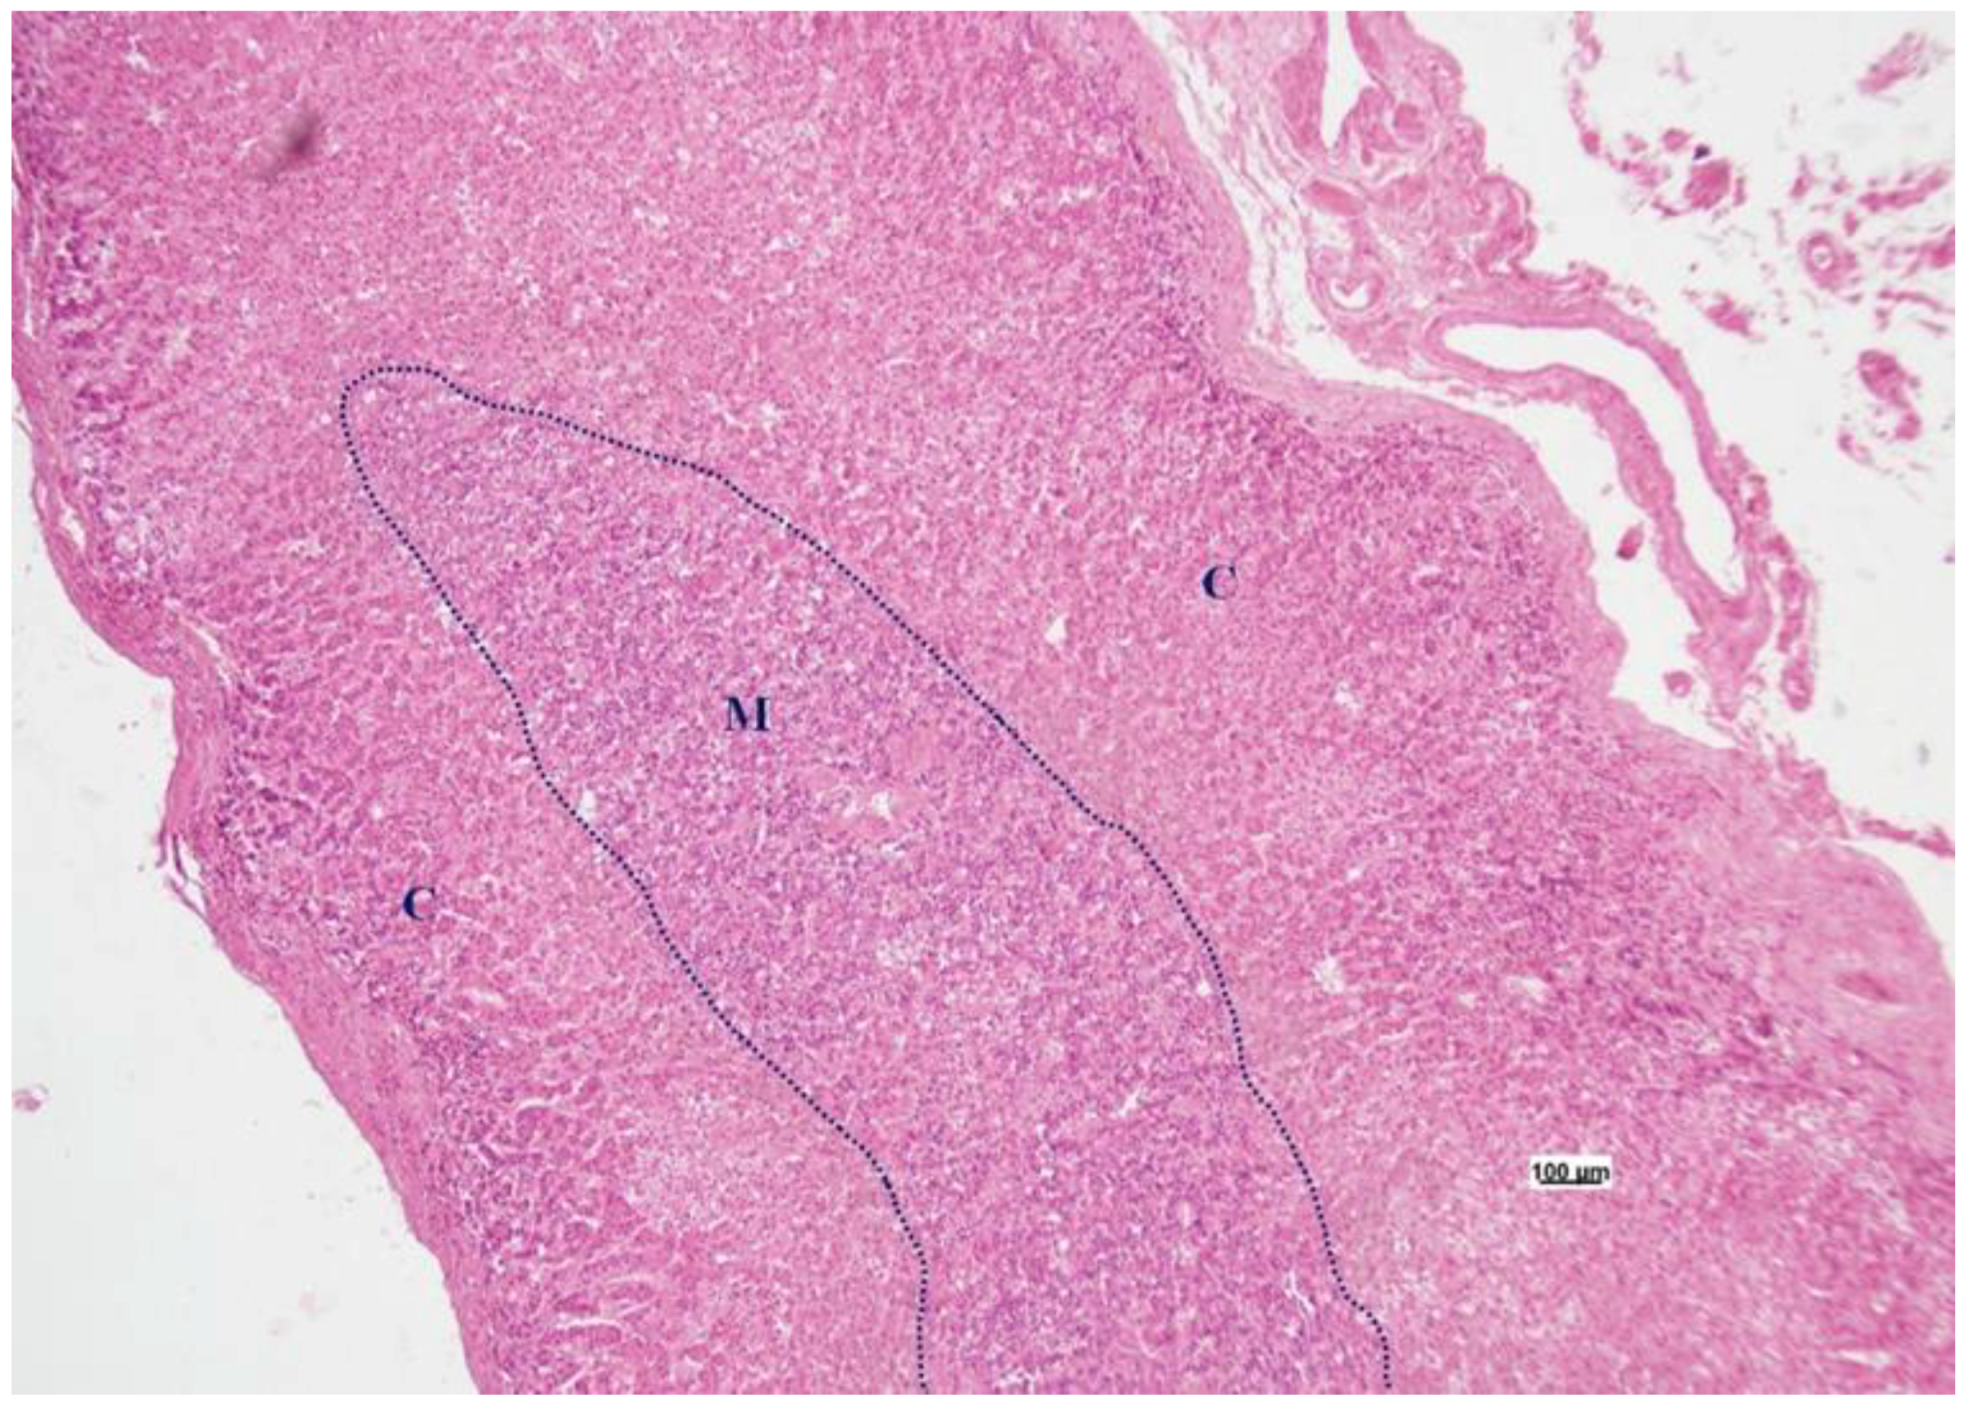

3.2. Histology